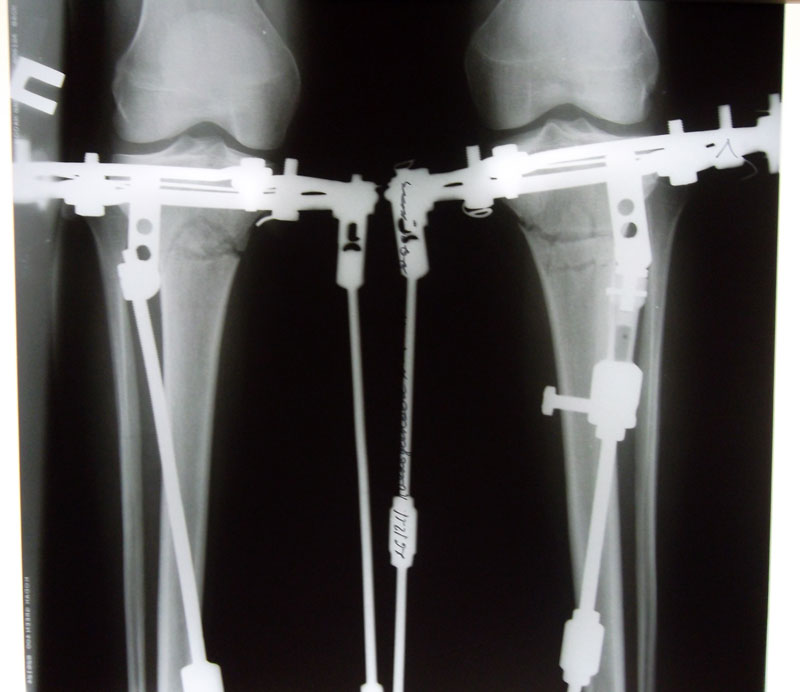

Здравствуйте, Николай Николаевич! Как и обещала, высылаю Вам снимки через 1 месяц с момента операции.

Здравствуйте, Румия! Рентгеновские снимки замечательные, всё идёт по плану.